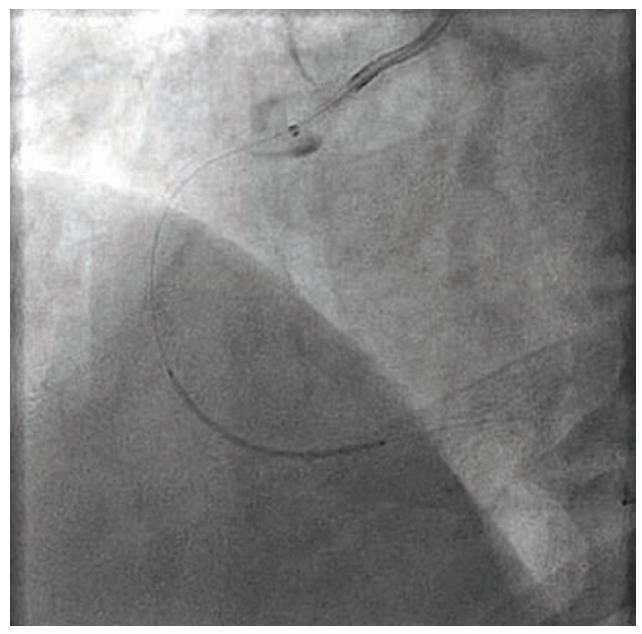

We then attempted to re-place the aforementioned 3.0 mm x 38 mm Synergy XD drug-eluting stent into the vessel; however, as the deployment attempt began, we could see that the balloon was not filling and the stent would not deploy. We attempted to remove the device from the coronary artery and out of the guiding catheter, but the stent shaft was entirely disrupted. In attempting to remove it, the distal stent and balloon and distal aspect of the shaft remained in the coronary in the ascending aorta, while the proximal aspect of the shaft was entirely free and so unexpectedly came out altogether (Figure 5). We attempted to snare the undeployed stent that was still on the wire with a Goose Neck snare (Medtronic), but were not able to get it past the undeployed stent, which was well seated on the stent deployment balloon. We placed a new .014-inch BMW wire distally past the stent, hoping to wrap it around the wire that was in the vessel distal to the stent and create a distal braid with both wires to pull the system out. However, we were not successful in gaining an adequate distal purchase. A Trapper balloon (Boston Scientific) was inflated in the distal aspect of the guide, trapping the distal stent shaft. Now trapped as a unit with the guide catheter, the distal stent shaft with the undeployed stent on the wire was removed without difficulty from the 6 Fr Slender sheath (Terumo) (Figure 6).